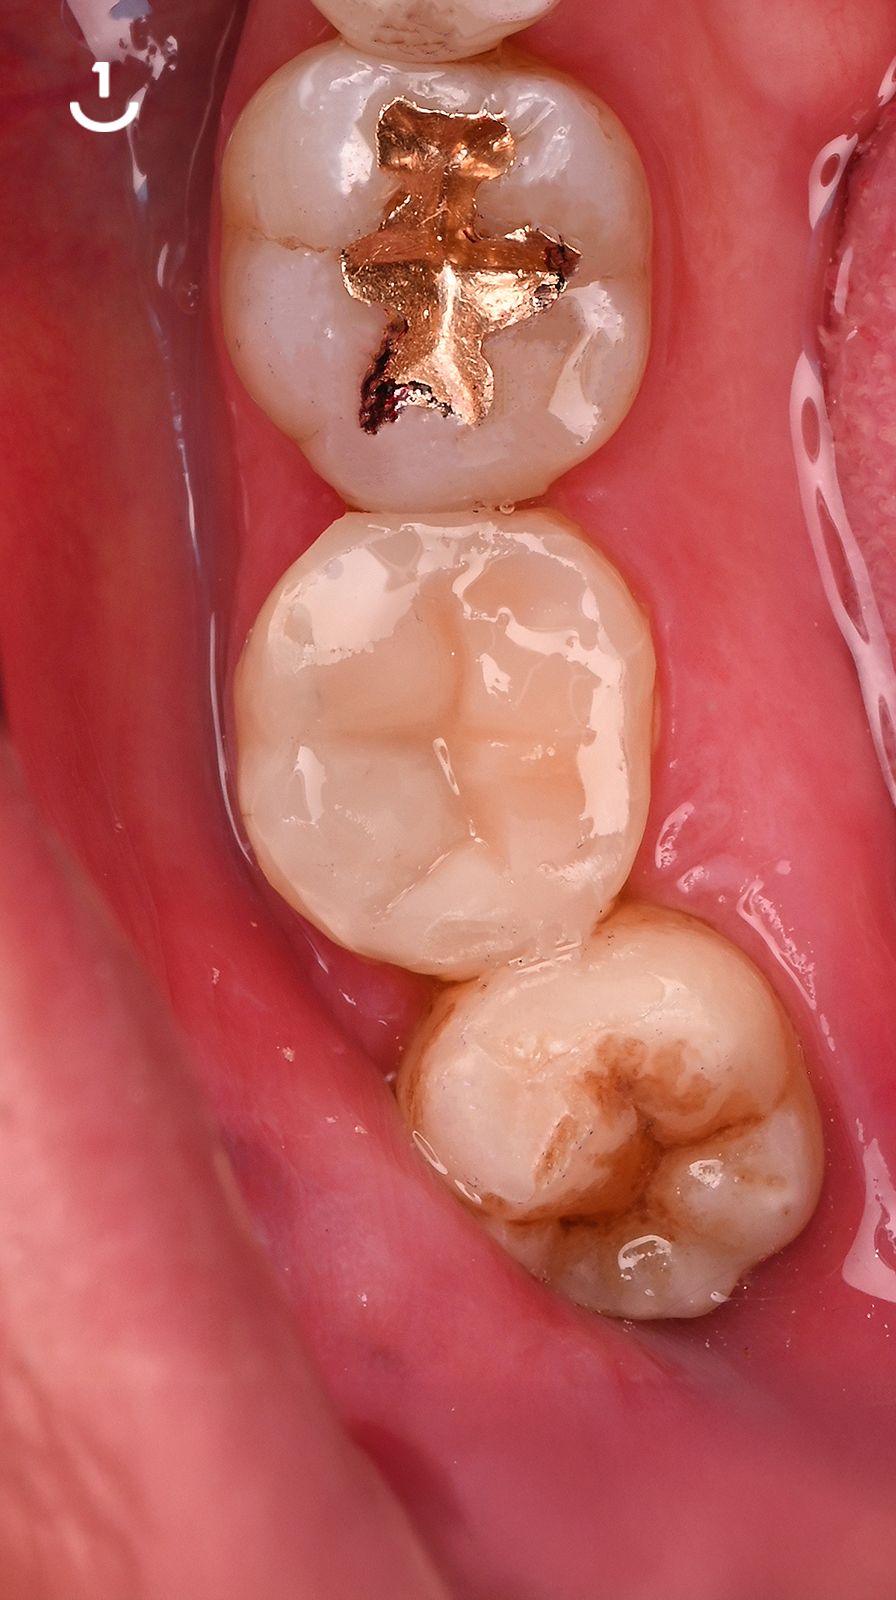

연세일등치과는 충치를 단순히 메우는 것보다

치아의 남은 구조를 얼마나 많이 보존할 수 있을지를

먼저 생각합니다.

치아

이를 위해 치료 전 단계부터 정밀한 진단을 통해

건강한 부위와 손상된 부위를 구분하고,

치료 범위를 필요한 만큼만 설정합니다.

이러한 보존 중심 접근은 단순한 철학이 아니라,

연세일등치과의 진료 시스템 그 자체입니다.

레진빌드업, 이러한 가치를 담아 진료합니다

보존 중심 접근 │ 자연치아의 건강한 부분을 가능한 보존하는 것을 목표로 진료 계획을 세웁니다.책임감 있는 진료 │ 상담부터 마무리까지, 모든 과정을 치과의사가 직접 세심하게 진행합니다.정밀 접착 과정 │ 치아와 재료가 긴밀하게 결합될 수 있도록 세심한 접착 단계를 거칩니다.자연스러운 조화 │ 주변 치아와의 색상이나 형태 등 전체적인 조화를 고려하여 수복을 진행합니다.